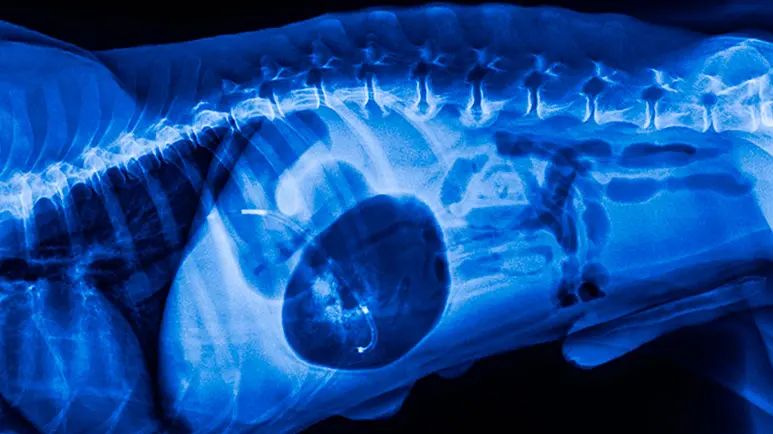

Veterinarians diagnose GDV with x-rays. Patients are first stabilized with IV fluids and oxygen, and an attempt is made to move the accumulated gas and fluid out of the stomach.